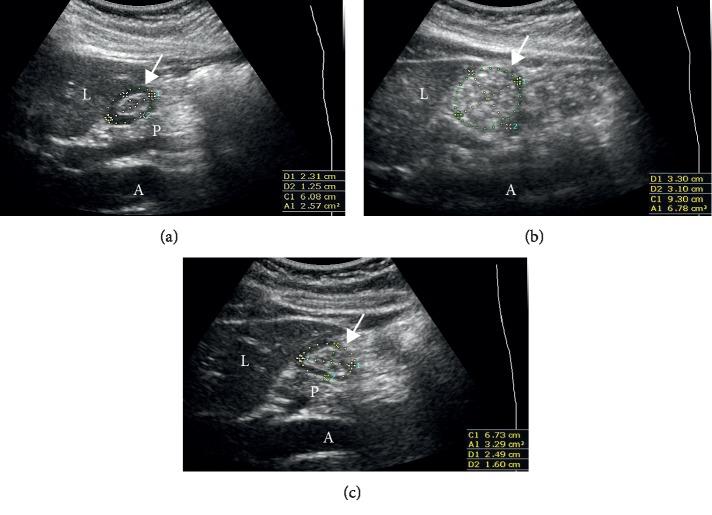

The aim of this prospective study was to evaluate the gastric emptying time of a rice-based meal by serial ultrasonography of the stomach. After baseline ultrasonographic assessment of ten fasted healthy volunteers, volunteers ingested standardized 420 g, 536 kcal rice-based meal (bibimbap), and serial evaluations were performed every hour until the stomach became empty. At baseline, all the participants had an empty stomach. The average time of complete gastric emptying of the rice-based meal was 5.8 ± 0.8 h (95% confidence interval (CI), 5.0 h to 6.5 h). Since the first postintake cross-sectional area (CSA) measurement, a decrease was observed, and CSA was maintained until postprandial 3-4 h ( > 0.05). It declined rapidly 4 h after meal intake (=0.031), reaching the nadir at approximately 6 h after meal intake. The gastric CSA and hunger score showed a positive correlation (correlation  = 0.616, < 0). The rice-based meal is emptied after 5.8 ± 0.8 h on average in healthy volunteers. Based on our results, 6.5 h (upper limit of CI) of fasting after the ingestion of a rice-based meal would be a safe preoperative fasting time, and this is in accordance with the current guidelines for preoperative fasting.

本前瞻性研究旨在通过胃的超声连续检查评估基于米饭的餐的胃排空时间。在对 10 名空腹健康志愿者进行基线超声评估后,志愿者摄入标准化的 420g、536kcal 基于米饭的餐(bibimbap),并在胃排空前每小时进行连续评估。在基线时,所有参与者的胃均为空。基于米饭的餐的完全胃排空平均时间为 5.8±0.8h(95%置信区间(CI),5.0h 至 6.5h)。自第一次餐后横截面积(CSA)测量开始,观察到 CSA 逐渐减少,并在餐后 3-4h 时保持不变(>0.05)。在用餐 4 小时后迅速下降(=0.031),在约 6 小时后达到最低点。胃 CSA 和饥饿评分呈正相关(相关系数=0.616,<0)。在健康志愿者中,基于米饭的餐平均在 5.8±0.8h 后被排空。根据我们的结果,在摄入基于米饭的餐后禁食 6.5h(CI 的上限)将是安全的术前禁食时间,这与目前的术前禁食指南一致。